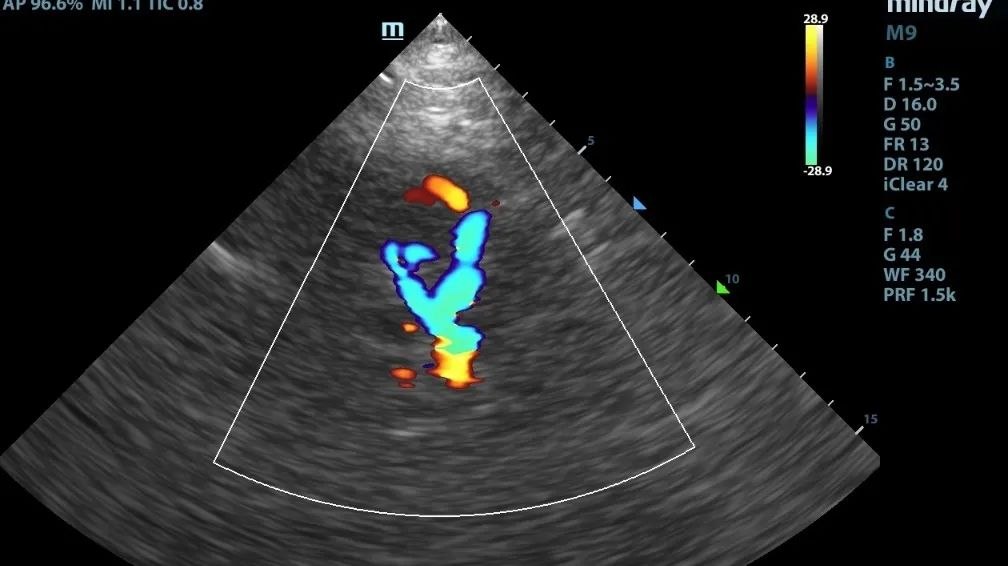

但是,TCCD就不一样了,它在TCD的基础上多了个彩色,也就是我们可以直观地看到颅内Villis环的彩色血流的走行及方向,因此就可以弥补TCD在使用上的一些不足。

TCCD图像能够显示大血管的走行及方向,更真实的反应血流速度